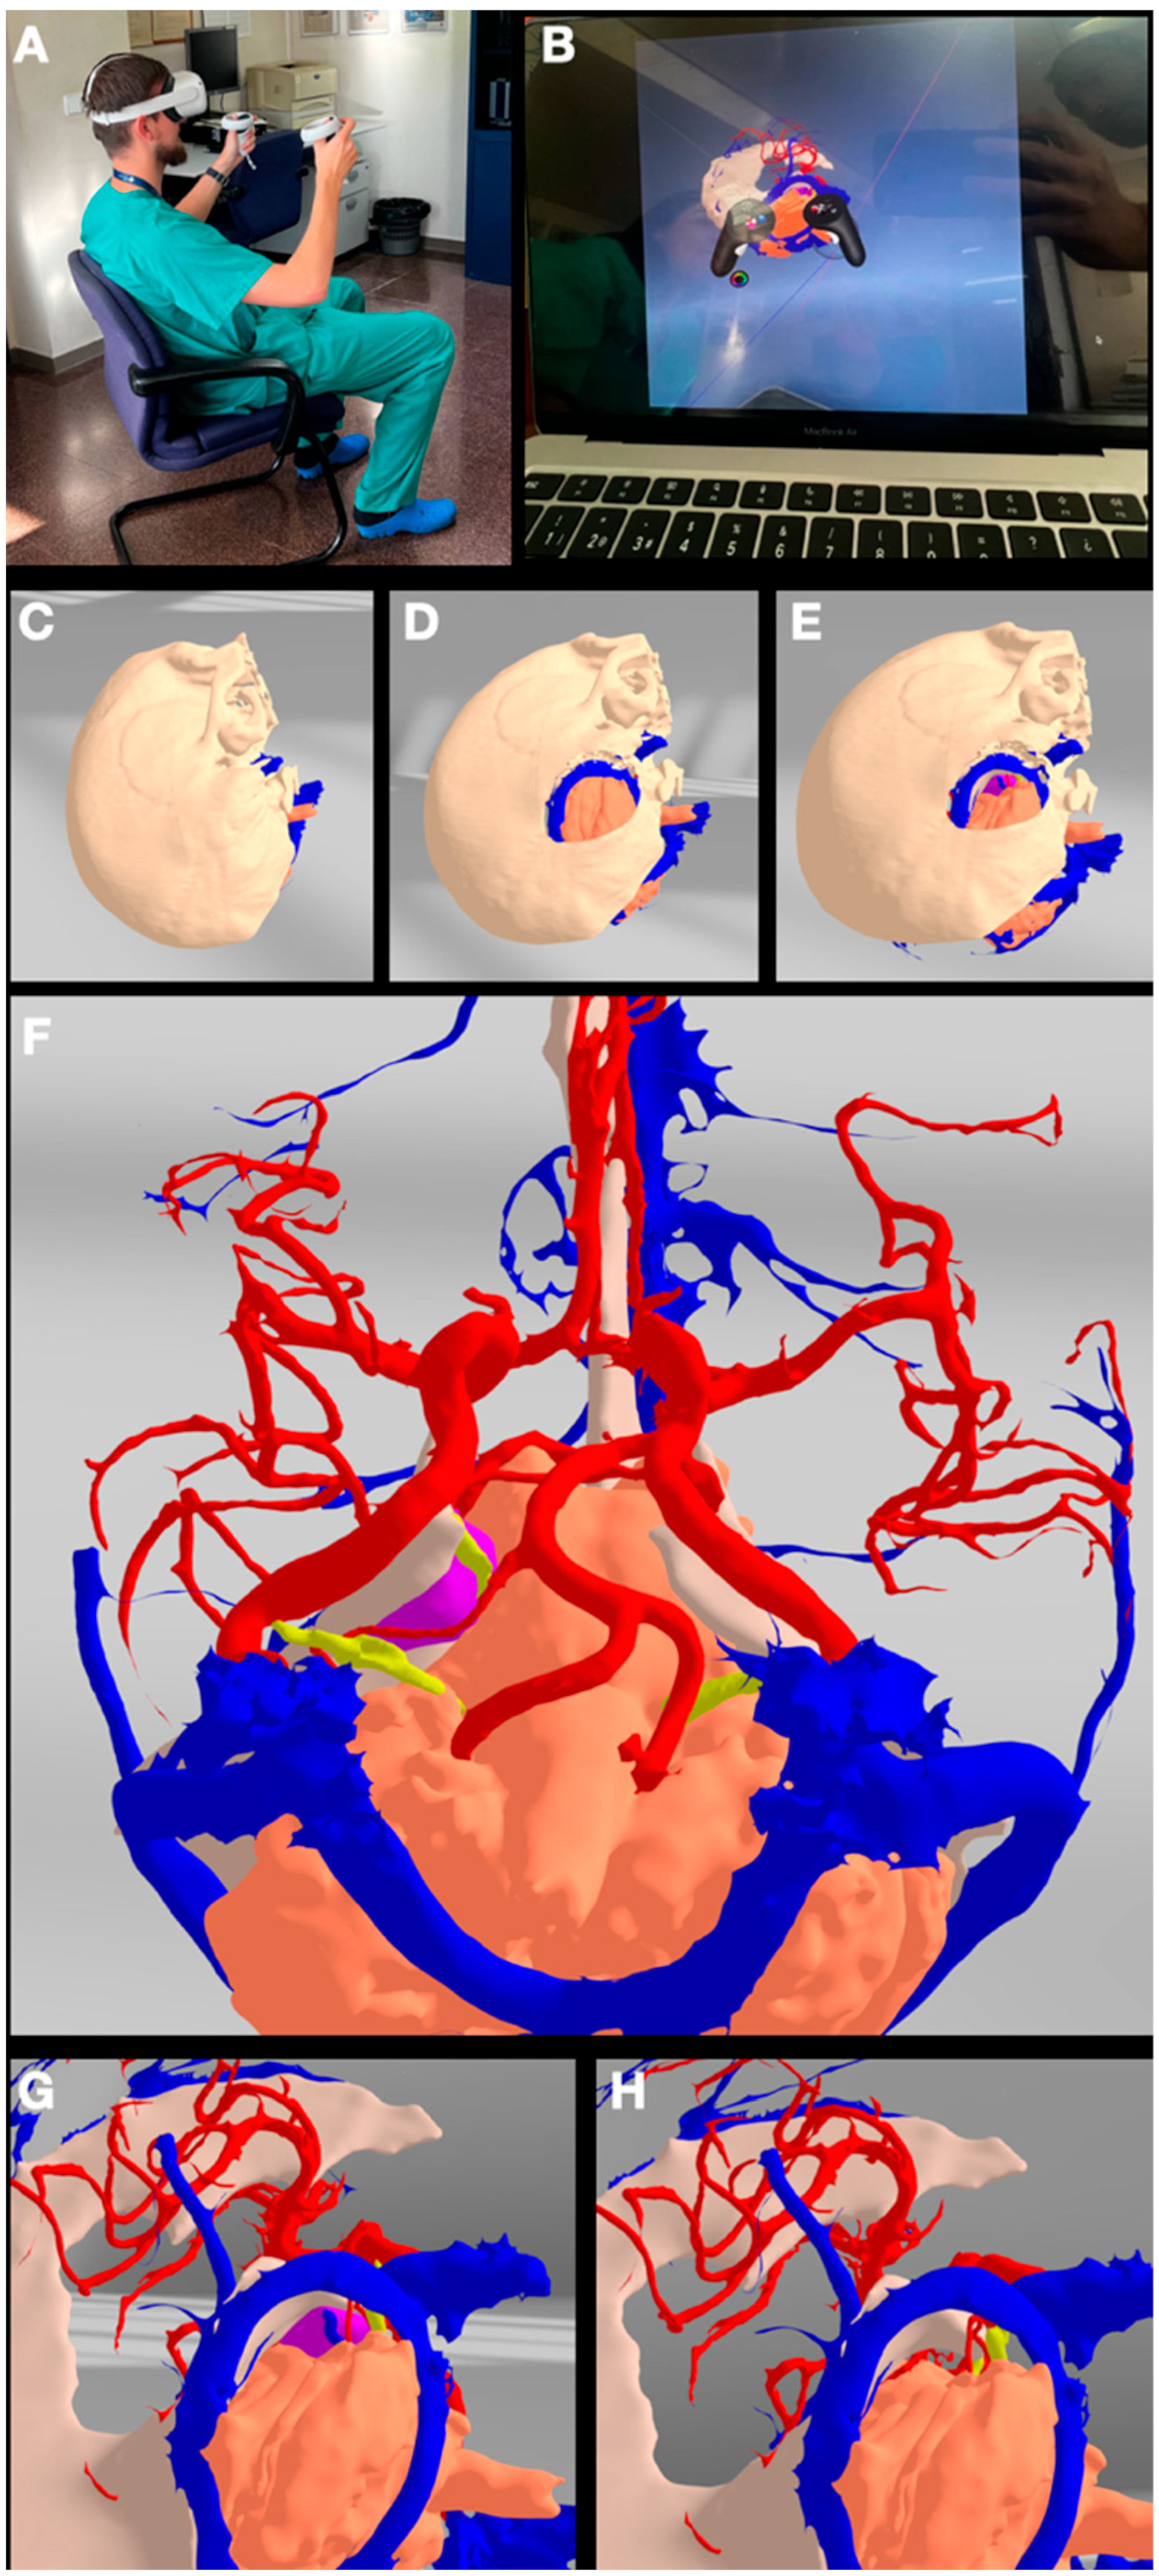

3.5. Case 5: Falcine Meningioma

4.2. Virtual Reality